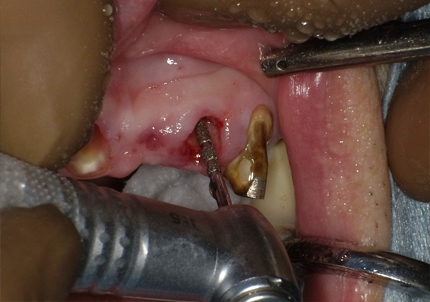

【右上1番SST 口蓋側歯根の抜歯】

【右上1番 SST インプラント埋入後に初期固定オステル値の測定】

← 右上1番 SST CT画像

※ CT画像にて歯根片が確認できる

【左上2番 SST 口蓋側歯根の抜歯】

← 左上2番 SST CT画像